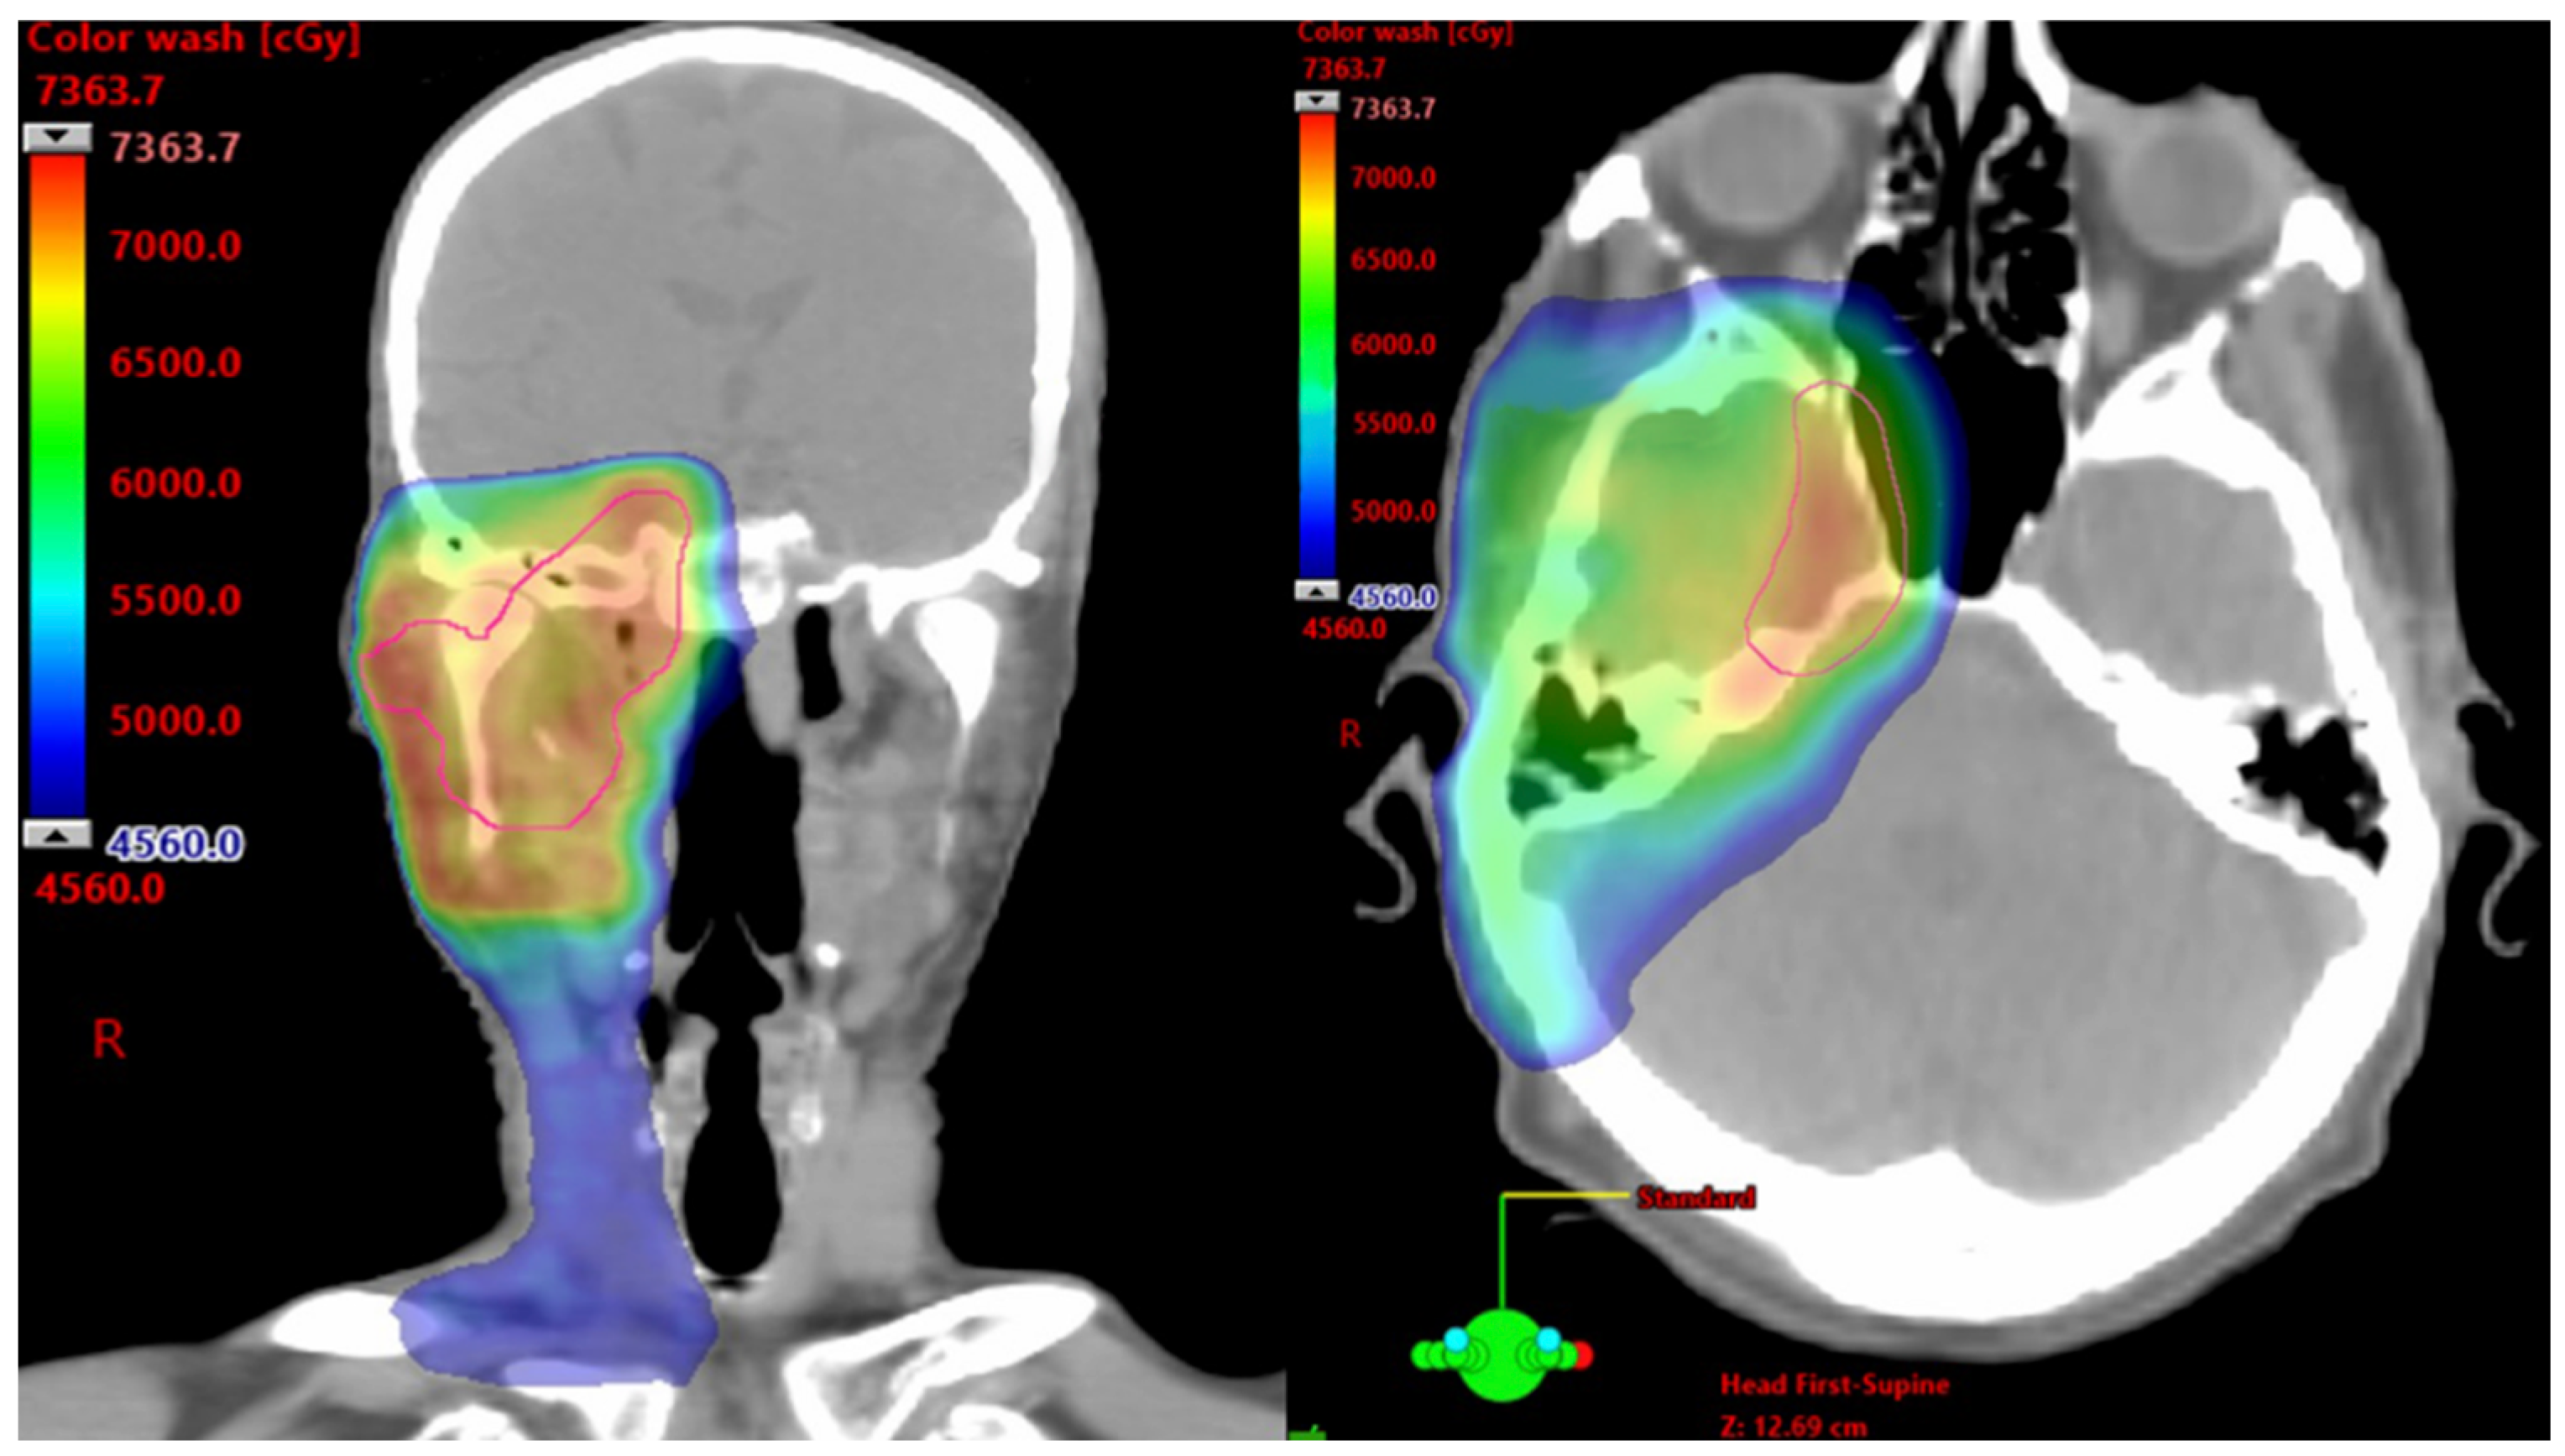

In patients with unresectable SCC and cPNI, RT has demonstrated durable local control rates exceeding 50%, even in advanced T4 disease [8,9]. However, much of this data predates immunotherapy. At some academic tertiary centers, neoadjuvant immunotherapy is now the preferred initial approach for patients with inoperable SCC and those who are poor surgical candidates due to comorbid conditions, functional limitations, or cosmetic concerns. This strategy promotes tumor shrinkage, organ preservation, and reduced toxicity from high-dose RT, particularly when tumors are near critical neurovascular structures, such as the brainstem or optic pathways. Figure 1 shows color wash dose distribution for a patient receiving definitive RT with volumetric modulated arc therapy after neoadjuvant cemiplimab. The patient showed a notable therapeutic response, with a reduction in gross disease along the third division of the trigeminal nerve to its root at the brainstem. This response enabled delivery of high-dose conformal RT while adhering to organ-at-risk constraints. Altered fractionation with volumetric modulated arc therapy and highly conformal RT techniques are typically used to mitigate acute and late toxicities. Nonetheless, given the proximity to critical structures and the extent of disease, complete elimination of risk remains challenging [30].

Figure 1.

Axial and Coronal Images From a Computed Tomography Planning Scan. Color wash dose distribution of a patient receiving 7320 cGy using a 120 cGy twice/day hyperfractionated approach to the right skull base and elective right neck.